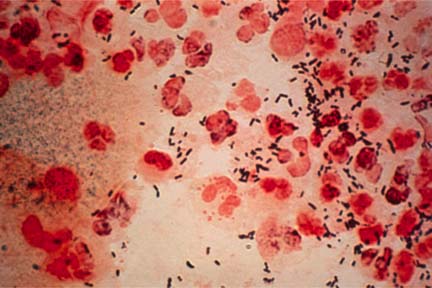

Gonoreea

Ce este?

Gonoreea este o infectie bacteriana grava. Barbatii pot avea arsuri cand urineaza

si o secretie din penis. Femeile pot avea secretii si iritatii vaginale, sau

dureri cand urineaza. Majoritatea femeilor si unii barbati nu vor avea semne

timpurii ale bolii.

Cum

se depisteaza?

Diagnosticarea poate fi facuta prin examinarea secretiilor la microscop.